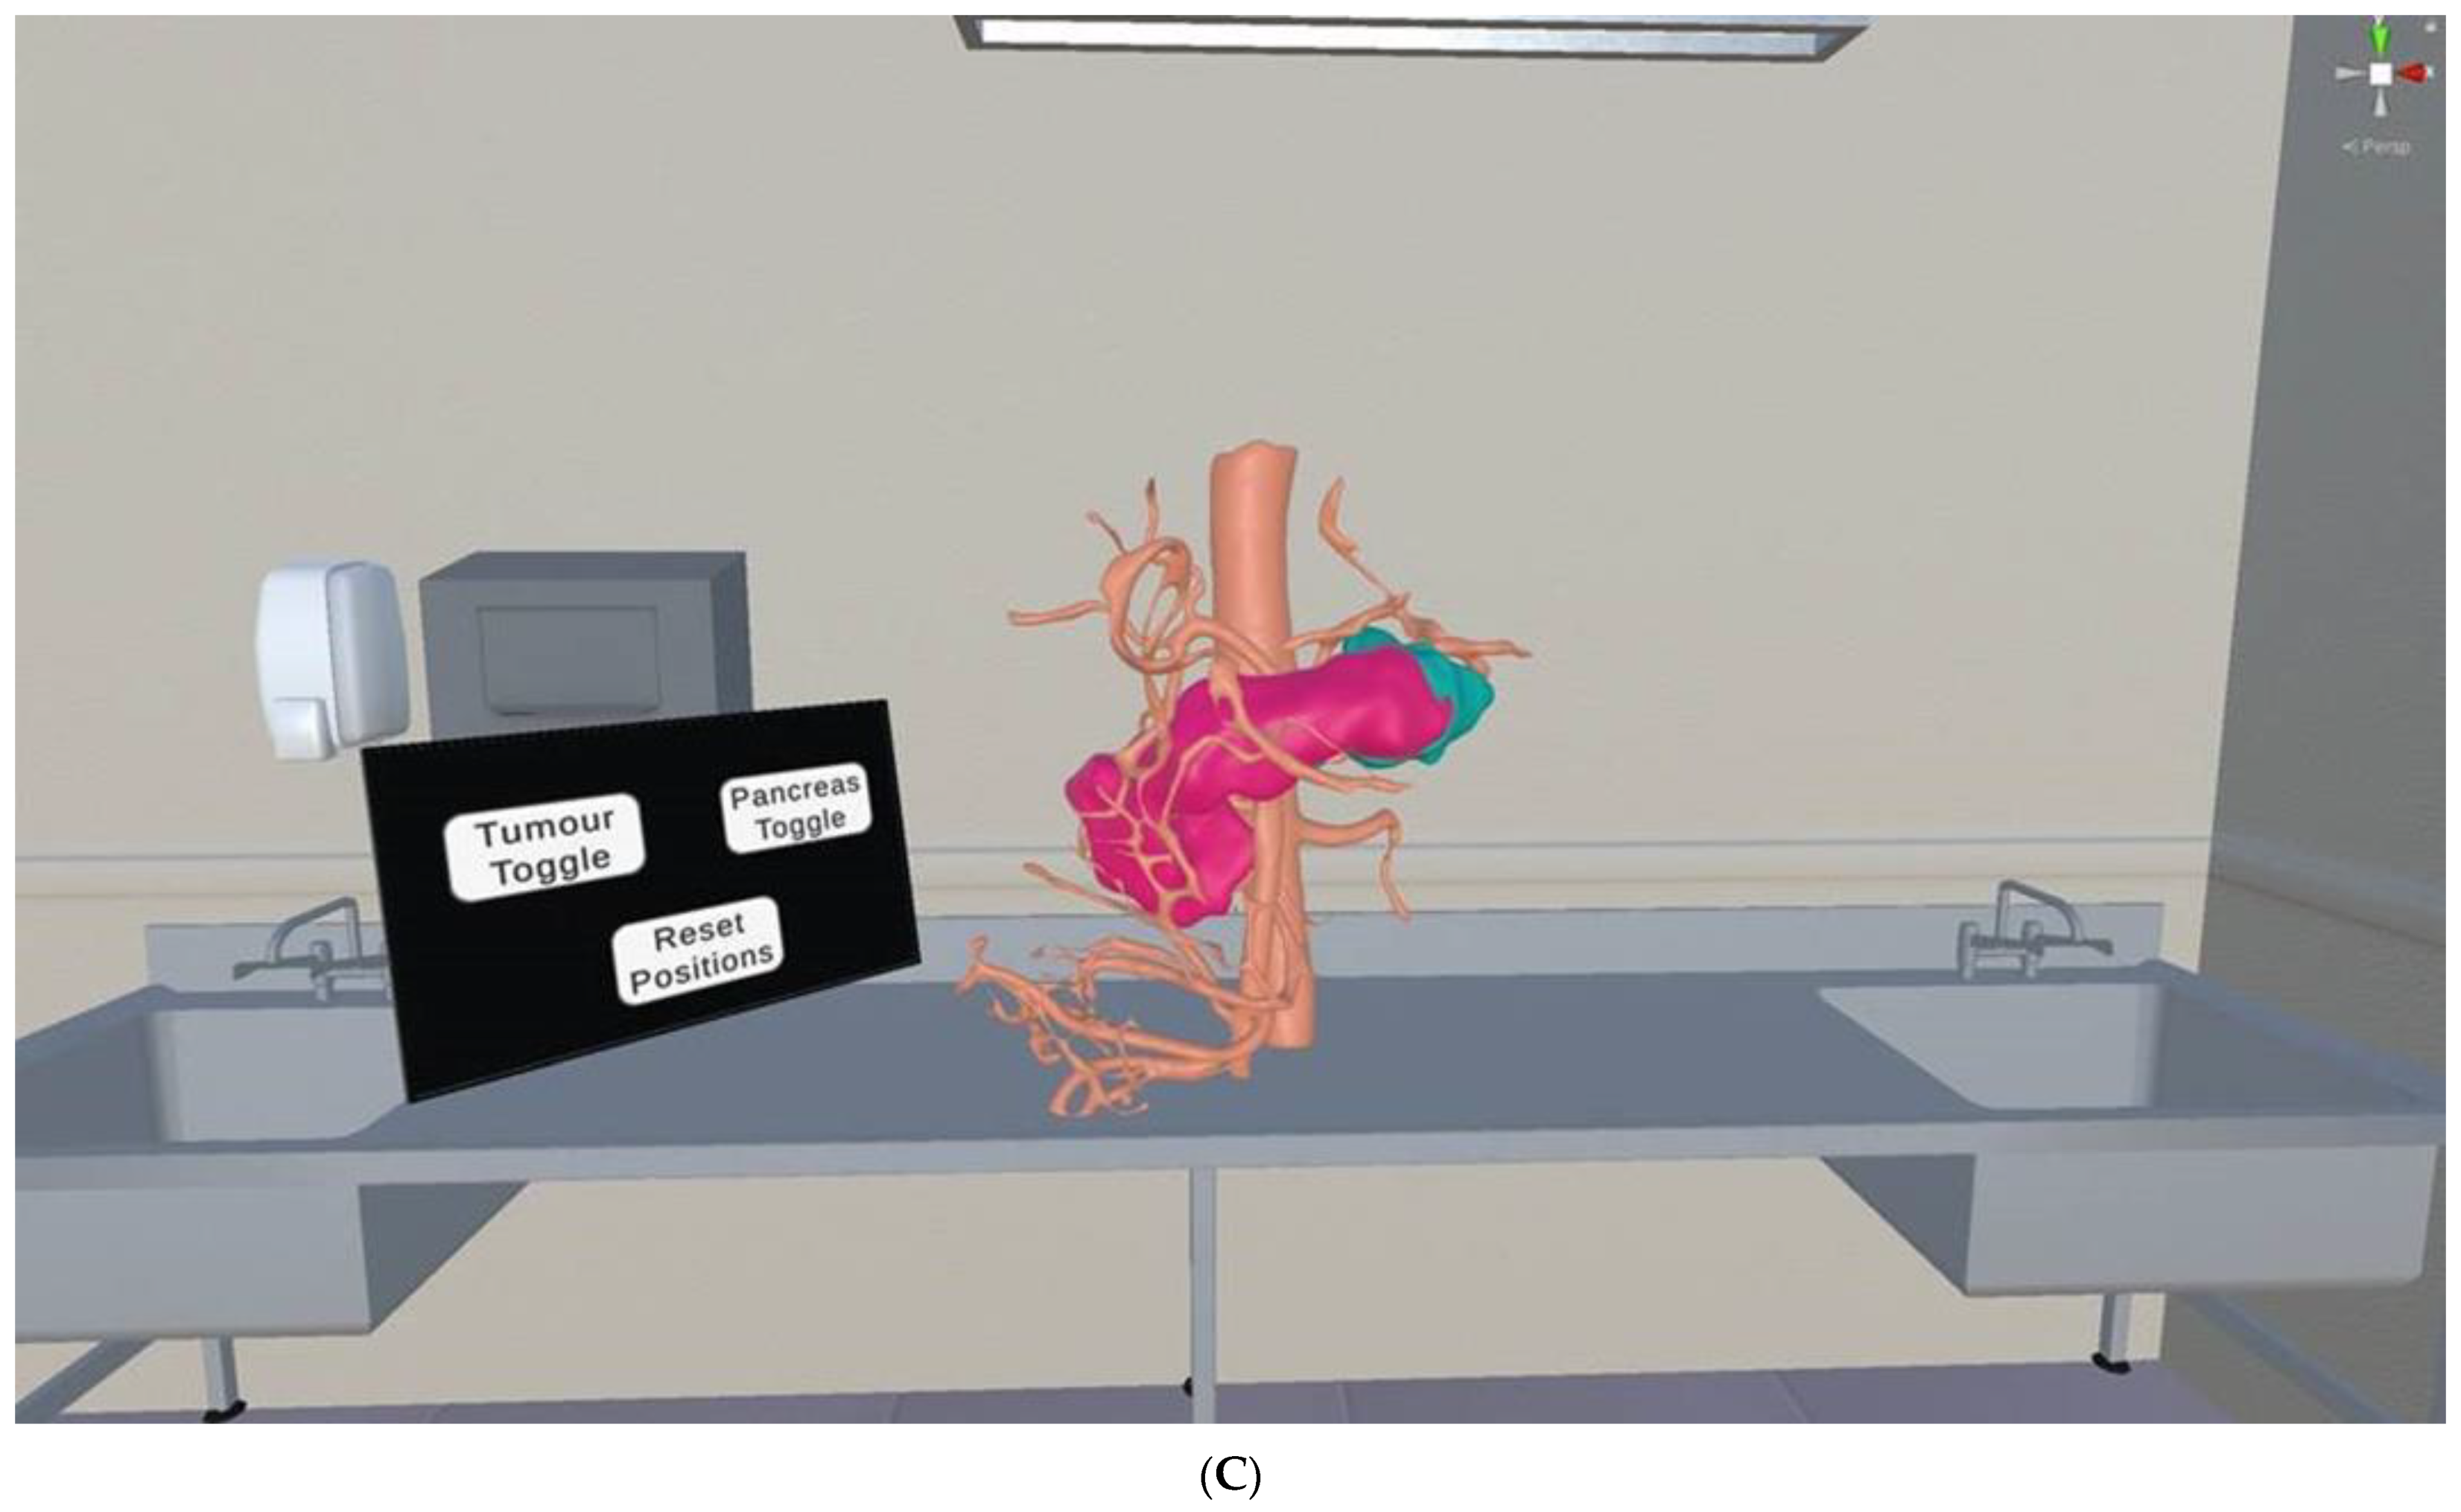

5.4. 3D-Printed Pancreatic Cancer Model

- Templin, R.; Tabriz, N.; Hoffmann, M.; Uslar, V.N.; Luck, T.; Schenk, A.; Malaka, R.; Zachmann, G.; Kluge, A.; Weyle, D. Case report: Virtual and interactive 3D vascular reconstruction before planned pancreatic head resection and complex vascular anatomy: A bench-to-bedside transfer of new visualization techniques in pancreatic surgery. Front. Surg. 2020, 7, 38. [Google Scholar] [CrossRef]

| Pancreas | 2: Pancreatic tumour: 1 Abdominal aorta and branches: 1 | CT | Pancreatic cancer for preoperative planning and education | Printer: Abdominal aorta and arterial branches were printed using Anycubic Photon S. Pancreatic tumour was printed using Raise3D N2 Plus. Materials: Abdominal aorta and arterial branches were printed with PU80A; Pancreatic tumour was printed with PLA Cost: USD 20 | Abdominal aorta and arterial branches were printed at a resolution of 47 μm x, y and z-axis planes. Pancreatic tumour was printed at resolution of 12.5 μm x, y and z-axis planes Time: ~20 h |